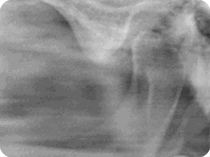

Die Gnathologie ist ein Teilgebiet der Zahnmedizin, das sich mit Erkrankungen der Kaumuskulatur bedingt durch Probleme der temporomandibulären Gelenke beschäftigt, die sich mit Geräuschen oder Schmerzen beim Öffnen und Schließen des Munds oder durch mandibulare Abweichung bemerkbar macht.

Diese sogenannten temporomandibulären Erkrankungen, können als Folge von Traumata, Bruxismus, Verlust von Teilen der Zähne oder systemischen Erkrankungen wie rheumatoide Arthritis entstehen.